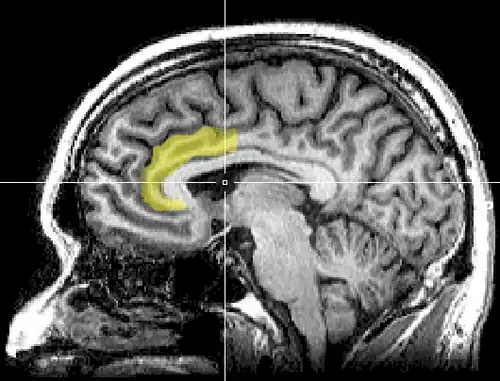

Cognitive dissonance produces a state of negative affect, which motivates the person to reconsider the causative behavior in order to resolve the psychological inconsistency that caused the mental stress.[130][131][132][133][134][135] As the affected person works towards a behavioral commitment, the motivational process then is activated in the left frontal cortex of the brain.[130][131][132][136][134]

The study Neural Activity Predicts Attitude Change in Cognitive Dissonance[138] (Van Veen, Krug, etc., 2009) identified the neural bases of cognitive dissonance with functional magnetic resonance imaging (fMRI); the neural scans of the participants replicated the basic findings of the induced-compliance paradigm. When in the fMRI scanner, some of the study participants argued that the uncomfortable, mechanical environment of the MRI machine nevertheless was a pleasant experience for them; some participants, from an experimental group, said they enjoyed the mechanical environment of the fMRI scanner more than did the control-group participants (paid actors) who argued about the uncomfortable experimental environment.[138]

The results of the neural scan experiment support the original theory of Cognitive Dissonance proposed by Festinger in 1957; and also support the psychological conflict theory, whereby the anterior cingulate functions, in counter-attitudinal response, to activate the dorsal anterior cingulate cortex and the anterior insular cortex; the degree of activation of said regions of the brain is predicted by the degree of change in the psychological attitude of the person.[138]

The Neural Basis of Rationalization: Cognitive Dissonance Reduction During Decision-making[50] (Jarcho, Berkman, Lieberman, 2010) applied the free-choice paradigm to fMRI examination of the brain's decision-making process whilst the study participant actively tried to reduce cognitive dissonance. The results indicated that the active reduction of psychological dissonance increased neural activity in the right-inferior frontal gyrus, in the medial fronto-parietal region, and in the ventral striatum, and that neural activity decreased in the anterior insula.[50] That the neural activities of rationalization occur in seconds, without conscious deliberation on the part of the person; and that the brain engages in emotional responses whilst effecting decisions.[50]

Emotional correlations

The anterior cingulate cortex activity increases when errors occur and are being monitored as well as having behavioral conflicts with the self-concept as a form of higher-level thinking.[143] A study was done to test the prediction that the left frontal cortex would have increased activity. University students had to write a paper depending on if they were assigned to a high-choice or low-choice condition. The low-choice condition required students to write about supporting a 10% increase in tuition at their university. The high-choice condition asked students to write in favor of tuition increase as if it were their completely voluntary choice. The researchers use EEG to analyze students before they wrote the essay, as dissonance is at its highest during this time (Beauvois and Joule, 1996). High-choice condition participants showed a higher level of the left frontal cortex than the low-choice participants. Results show that the initial experience of dissonance can be apparent in the anterior cingulate cortex, then the left frontal cortex is activated, which also activates the approach motivational system to reduce anger.[143][144]